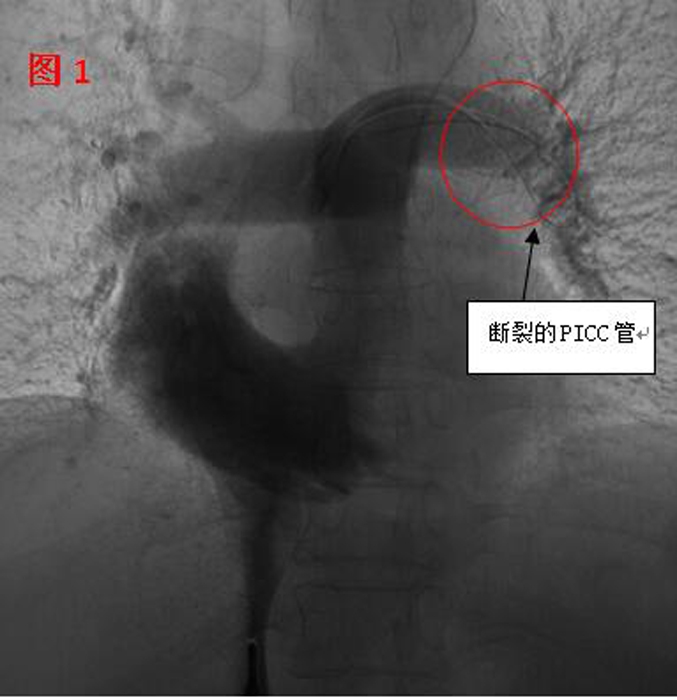

??? 11月2日,在醫(yī)院多個(gè)科室的配合下,這臺(tái)心臟異物取出術(shù)開(kāi)始了。血管外科醫(yī)生在手術(shù)時(shí)發(fā)現(xiàn),斷裂的PICC管竟完全移位至病人的心室、肺動(dòng)脈(見(jiàn)圖1),情況十分棘手。術(shù)中應(yīng)用異物捕捉系統(tǒng)時(shí),由于導(dǎo)管隨心臟跳動(dòng)和呼吸的影響,擺動(dòng)巨大,捕捉后導(dǎo)管反復(fù)滑脫,且術(shù)中患者心臟稍受刺激就會(huì)出現(xiàn)心律失常。